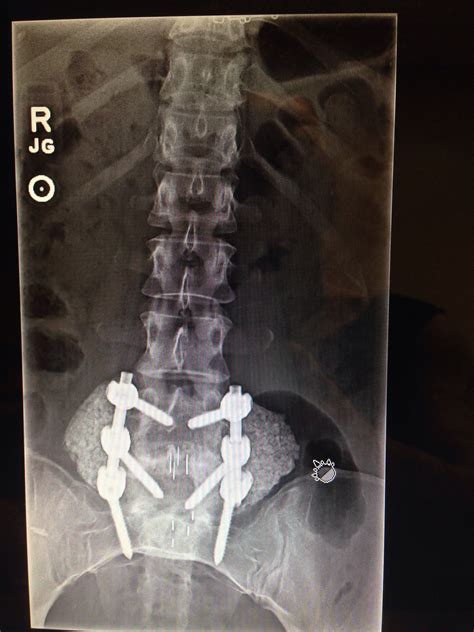

• Consultation and Evaluation: Patients will undergo a thorough evaluation, including medical history, physical examination, and diagnostic tests such as X-rays, MRI, or CT scans.

• Fixation: Plates, screws, or other fixation devices may be used to stabilize the vertebrae and promote fusion.